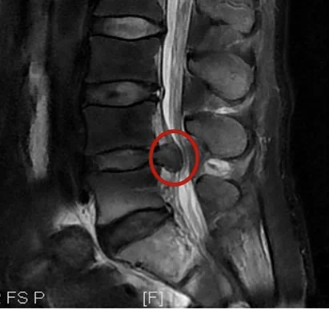

腰椎间盘突出指腰椎间盘的纤维环因退变或外力作用发生破裂,导致髓核向后方(椎管内)突出的一种影像学表现,常见于CT或MRI检查结果中,属于病理改变(这种病理改变不一定伴随临床症状,部分患者可能仅表现为影像学异常)。